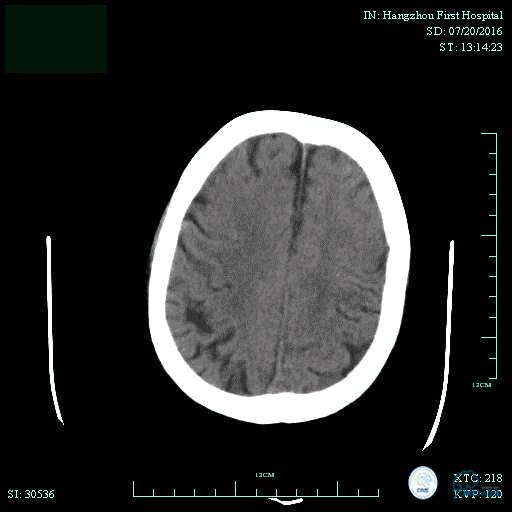

辅助检查:血常规、生化、凝血功能未见明显异常,心电图:窦性心律,ST-T改变;头颅CT平扫:未见明显出血。头颅MRI:未见新鲜梗塞灶;头颅MRA:双侧大脑前动脉远端缺如。

术前头颅CT平扫。

术后头颅CT复查。